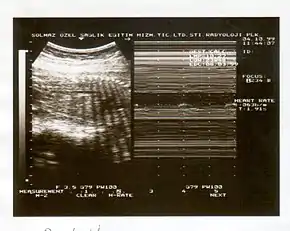

A biophysical profile (BPP) is a prenatal ultrasound evaluation of fetal well-being involving a scoring system,[1] with the score being termed Manning's score.[2] It is often done when a non-stress test (NST) is non reactive, or for other obstetrical indications.

The BPP has five components: four ultrasound (US) assessments and an NST. The NST evaluates fetal heart rate and response to fetal movement. The five discrete biophysical variables are:

- Fetal heart rate